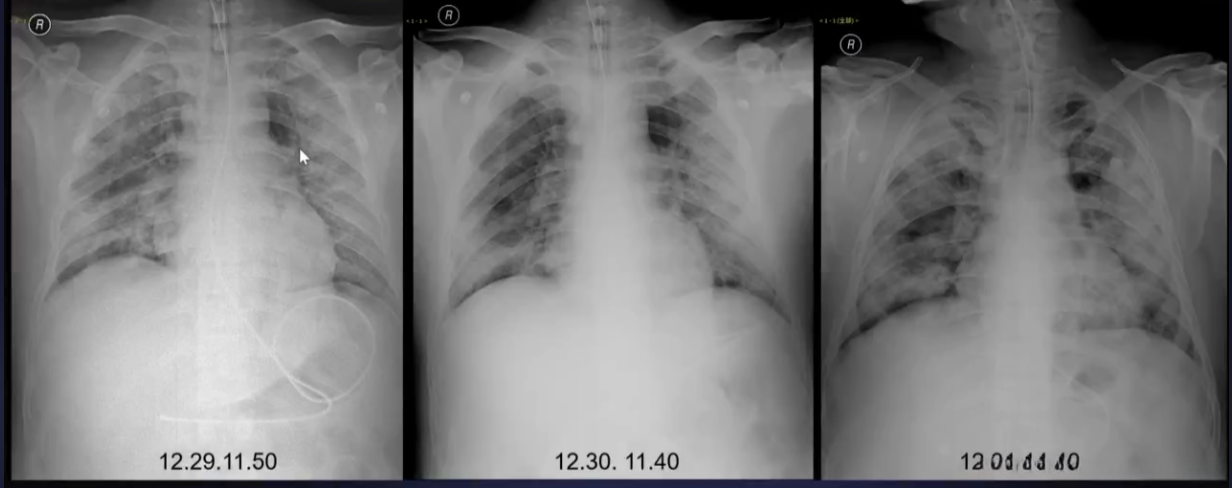

- 重症:双肺弥漫性浸润,实变+磨玻璃影,少量胸水等

CT患者某一加重过程

重型表现